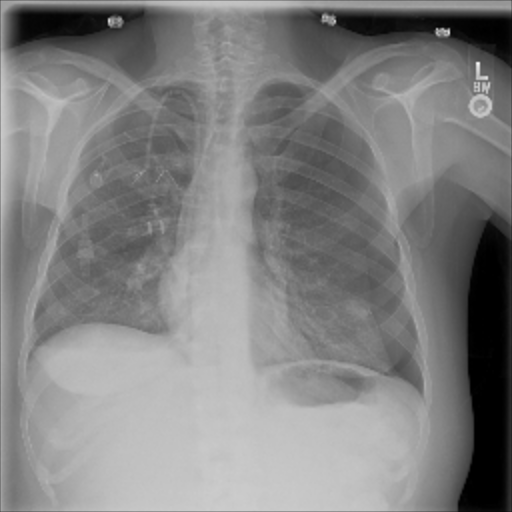

The data used in the following experiments consists of DICOM X-ray images, obtained from the University of Washington Medical Center and affiliated institutions, centered in Seattle by scanning radiology reports from the last three years. Inclusion criteria were: (i) Digital Radiography (DR) images, (ii) Chest radiographs, (iii) Posterior-anterior or anterior-posterior view position, (iv) Adult patients. Any personal health information was removed. Image-level labels were derived from natural-language processing based analysis of the reports. Cases were partially reviewed by a radiologist to confirm appropriate finding in the report’s impression section and this represented a critical finding. The resulting dataset contained 1003 images: 437 with pneumothorax, 566 with a different or no abnormality detected. We generated pixel-level annotations of the pneumothorax region for 305 of the positive cases. For training and evaluation, we divided the dataset into five cross-validation splits of similar size, such that images of the same patient resided in the same split.

The pre-trained ResNet-50 was also employed as the patch-level classifier within the MIL approach. We chose the binary cross-entropy between the maximum patch score and the image-level label as the loss function. The batch size was selected as the number of patches per image. We trained with an initial LR of for 30 epochs and achieved an average AUC of 0.930.01 using this method. High patch scores (indicated by thicker red frames, cf. Fig. 5(c)) give a hint on the location of the pneumothorax.

As pixel-level ground truth annotations were available only for a subset of the images, 871 images in total were used for training the FCN for 400 epochs. As a loss function, a weighted cross entropy (25.0 for pneumothorax pixels and 0.5 for non-pneumothorax pixels in order to account for the smaller size of pneumothorax regions) was employed at pixel-level with an initial LR of . With an average AUC of 0.920.02, the overall performance of this method is worse than the CNN and MIL. On the other hand, the FCN generates pixel-level probabilities (cf. Fig. 5(d)), which indicate the location of the pneumothorax. The average Dice coefficient for positively classified cases is .